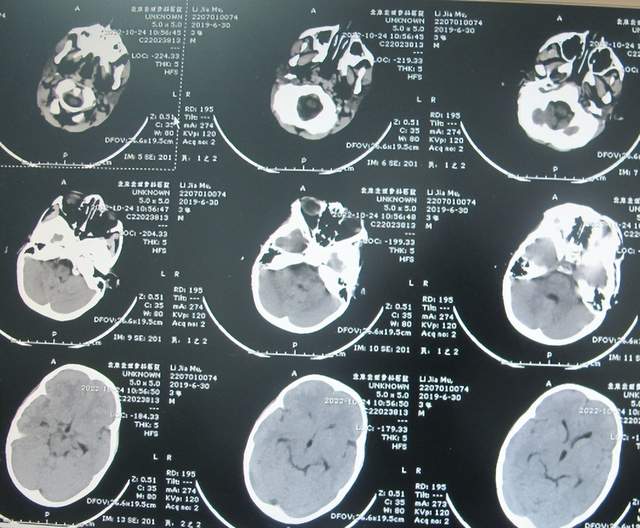

入院次日进行了脑室外引流术(图-9);引流出的脑脊液浑浊有絮状物(图-10)。

图-9:2022年7月2日头颅CT

图-10:2022年7月2日